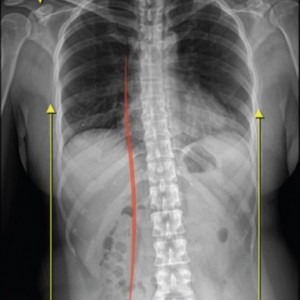

01.

척추

척추측만증 또는 좌, 우 한쪽으로 기울어진 척추로 인해 체중이 한쪽 허리로 집중된다면 장기적으로 체중이 기울어진 쪽 허리에 뼈가 자라거나 퇴행성 변화가 빠르게 진행됩니다.